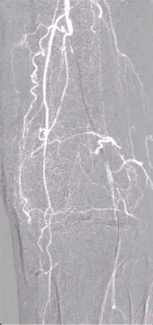

Peripheral vascular disease (PVD), specifically in its more advanced forms such as chronic limb-threatening ischemia (CLTI), presents a great clinical challenge. Endovascular interventions have become the primary approach for...